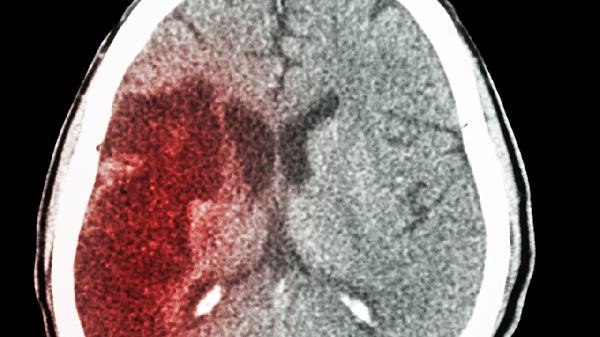

脑出血恢复期的治疗主要包括药物治疗、康复训练、生活方式调整、心理干预和定期复查等方式。脑出血恢复期通常与出血量、出血部位、患者基础健康状况等因素有关,可能表现为肢体功能障碍、语言障碍、认知障碍等症状。

定期复查包括头颅CT或MRI检查、血压监测和血液检查等。通过定期复查可以评估恢复情况,及时发现并处理可能出现的并发症。复查频率应根据医生建议进行,通常出院后1个月、3个月、6个月各复查一次,之后每半年复查一次。